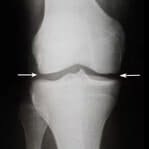

Antes

Después

1 mes